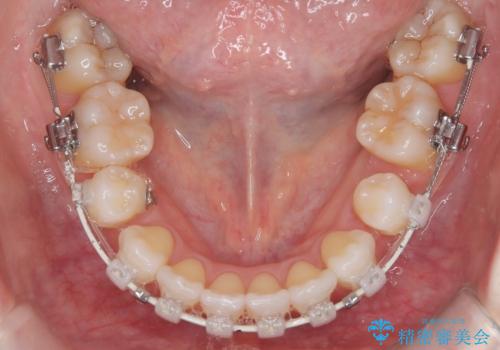

ハーフリンガル矯正|上下4本の抜歯で叢生を改善し、美しい歯並びへ

- 患者様は、歯並びの乱れ(叢生)を整えたいが、前歯の突出感は気にならないとのことで来院されました。診察の結果、全体的な歯列のスペース不足により抜歯が必要と判断。しかし、前歯を大きく下げる必要はなかったため、小臼歯の中でも5番(第二小臼歯)を抜歯する治療計画を立てました。装置は、上顎が舌側(リンガル)、下顎が表側(審美ワイヤー)のハーフリンガル矯正を採用し、目立ちにくさと効率的な歯の移動を両立しました。

抜歯によって歯を並べるためのスペースを確保。その後、ハーフリンガル矯正を用いて、上顎は舌側から、下顎は目立ちにくいワイヤーで歯を誘導し、歯列全体を整えました。治療期間を通じて、噛み合わせのバランスも改善し、機能的にも審美的にも理想的な仕上がりとなりました。患者様からは「目立たずに矯正でき、きれいな歯並びになって嬉しい」とご満足いただきました。